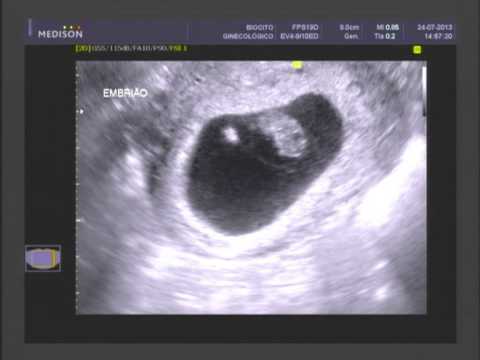

Bebés de 8 semanas. É possível saber o sexo do bebê a partir da 8ª semana de gravidez através de um exame de sangue específico sexagem fetal ou a partir da 13ª semana pelo ultrassom. Na ultrassonografia transvaginal a depender da posição do feto e da implantação.

Há um grande espaço entre a parede uterina e o feto. Na 8ª semana de gravidez concretamente o teu útero tem já o tamanho de uma toranja enquanto antes da gravidez as suas dimensões seriam como as de um punho. No desenvolvimento de um bebê de 8 semanas você pode se surpreender quando ver seu pequeno repentinamente em silêncio.

O bebê com 8 semanas de gestação se movimenta bastante dentro do útero da mamãe porém não é possível senti-lo ainda. Tu bebé tiene las muñecas flexionadas y las manos unidas sobre el corazón. Por otro lado la cola del embrión empieza a desaparecer y acabará siendo reemplazada por los cuatro huesos unidos que formarán el coxis o parte inferior de la columna del bebé.